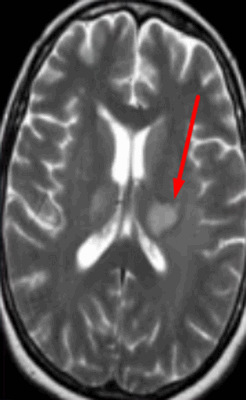

Туберозный склероз. Субэпендимальные узлы. Аксиальная Т-зависимая МРТ.

Субэпендимальные, то есть проецирующиеся в желудочек, но растущие со стороны паренхимы мозга, узлы чаще расположены рядом с хвостатым ядром или гипоталамической бороздой сразу за отверстием Монро, реже в области III, IV желудочков и Сильвиева водопровода. На Т2-взвешенных томограммах субэпендимальные узлы умеренно гиперинтенсивны и часто содержат кальцинаты . От астроцитом их отличает не столь яркий сигнал и меньшие размеры. Контрастирование при введении препаратов гадолиния иногда наблюдается и в субэпендимальных узлах , и всегда в астроцитомах.